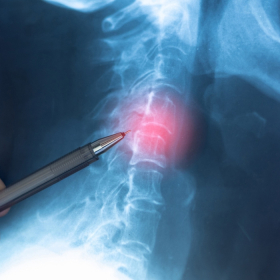

Hiện nay vẫn chưa tìm ra chính xác nguyên nhân ung thư tủy sống